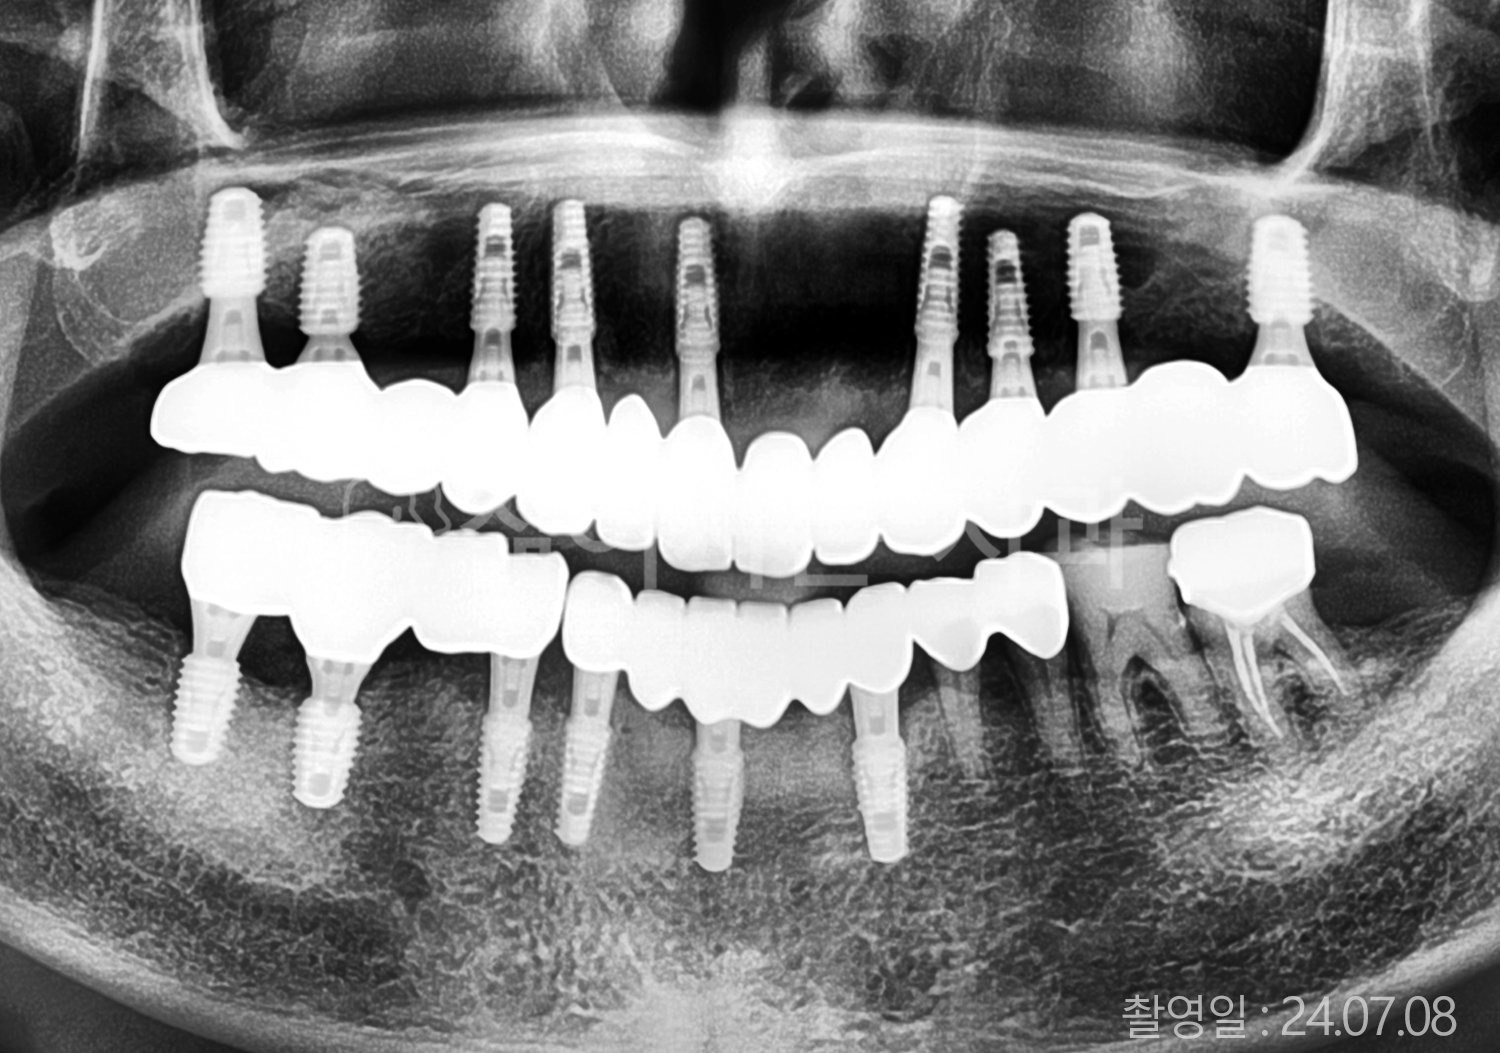

• 80대 전체치아 10개 이상 임플란트

• 60대 고혈압, 당뇨, 고지혈증 전체치아 10개 이상 임플란트

• 60대 전체치아 10개 이상 임플란트

• 60대 고혈압, 고지혈증 전체치아 10개 이상 임플란트

• 50대 고혈압, 당뇨, 고지혈증 전체치아 10개 이상 임플란트

• 70대 골다골증, 파킨스병 전체치아 10개 이상 임플란트

• 40대 전체치아 10개 이상 임플란트

• 60대 골다골증 전체치아 10개 이상 임플란트

• 40대 고혈압 전체치아 10개 이상 임플란트

• 50대 전체치아 10개 이상 임플란트

• 70대 전체치아 10개 이상 임플란트